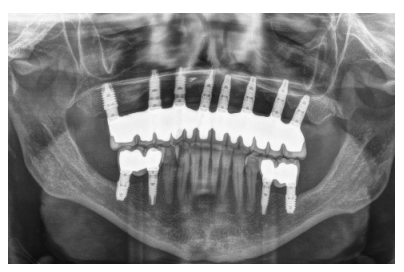

Cuatro meses después de la cirugía inicial de regeneración del maxilar se lleva a cabo un nuevo Cone-beam dental, en el que se planifica la siguiente fase de la cirugía en función de la ganancia ósea que se ha logrado con los injertos en bloque y la técnica de Split en dos fases. En las imágenes podemos observar como en las zonas de máxima atrofia, donde se colocan los bloques se ha logrado una anchura que triplica la inicial (Figuras 19 y 20). En la apertura del colgajo se observa como las imágenes del TAC de planificación se corresponden con la realidad, y además que la zona tratada mediante Split en dos fases ha logrado también una anchura de cresta que ahora permite la retirada de los implantes transicionales y la inserción de nuevos implantes en esta posición, con una mejor situación de partida y eje para la confección posterior de la prótesis (Figuras 21-22). Se procede a la inserción de los implantes y se realiza una prótesis provisional de carga progresiva apoyada en los implantes colocados en la primera fase quirúrgica. De este modo, la paciente puede tener una prótesis fija sobre implantes que servirá para ir dando forma a los provisionales en cuanto a estética y función de cara a la prótesis definitiva (Figuras 23-24).

Cuatro meses después se procede a la carga de los implantes insertados en esta segunda fase quirúrgica. De nuevo se opta por unas segundas prótesis provisionales de carga progresiva, elaboradas del mismo modo que las anteriores Tres meses después la oclusión está preparada para la confección de la prótesis definitiva, por lo que se transforma la prótesis en una prótesis metal-cerámica, atornillada sobre transepitelial confeccionada mediante cad-cam (Figuras 25-26). La paciente ha recuperado la función demandada, así como la corrección de la oclusión de la prótesis completa, que presentaba una mordida cruzada lateral derecha con disminución de la dimensión vertical al inicio del tratamiento. La paciente acude a sus revisiones y el tratamiento se mantiene estable tal como se muestra en las imágenes tomadas a los 10 años de seguimiento (Figuras 27-28).